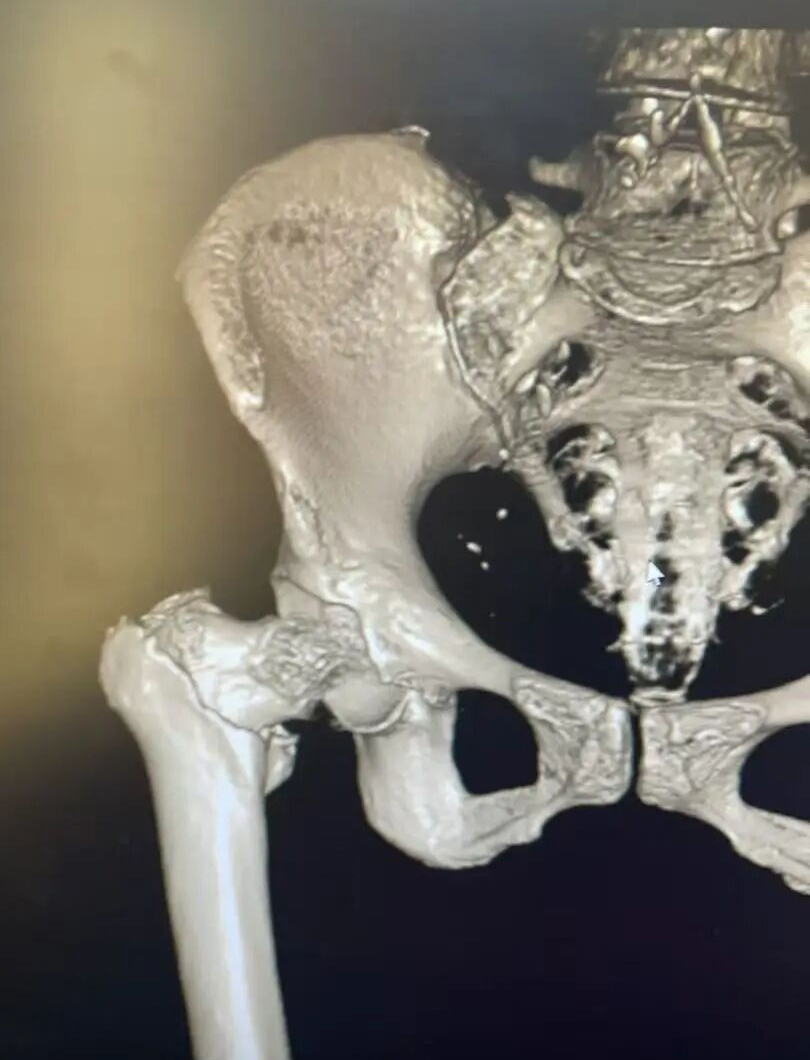

患者术前影像

门诊CT 检查结果明确:右股骨粗隆间粉碎性骨折。骨科团队结合俞大娘的病史、症状及影像检查,综合评估其身体状况后,同样为其制定了 “闭合复位 PFNA 内固定术” 方案。